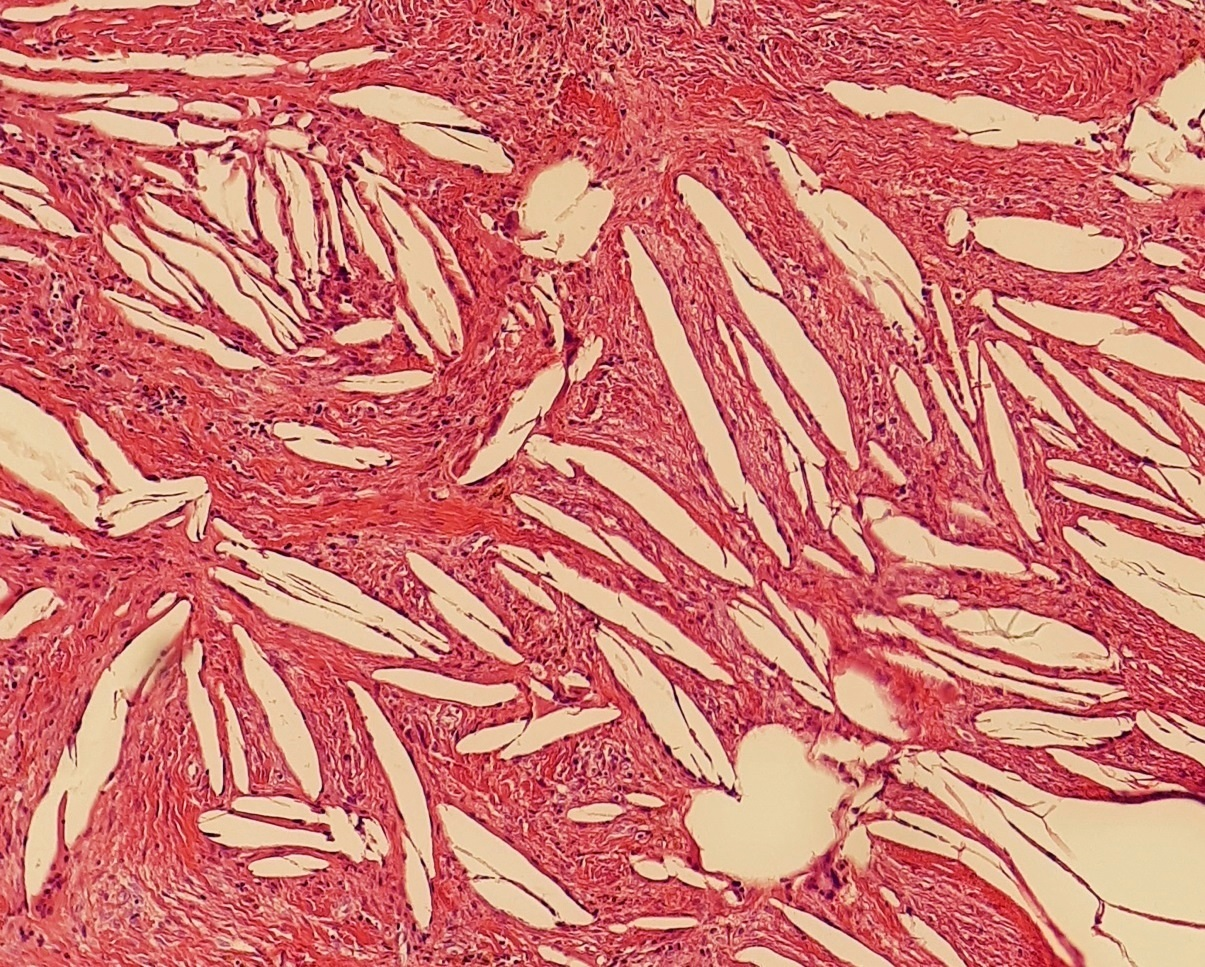

- cholesterol clefts

- 齒源 → Rushton bodies

- Rushton bodies